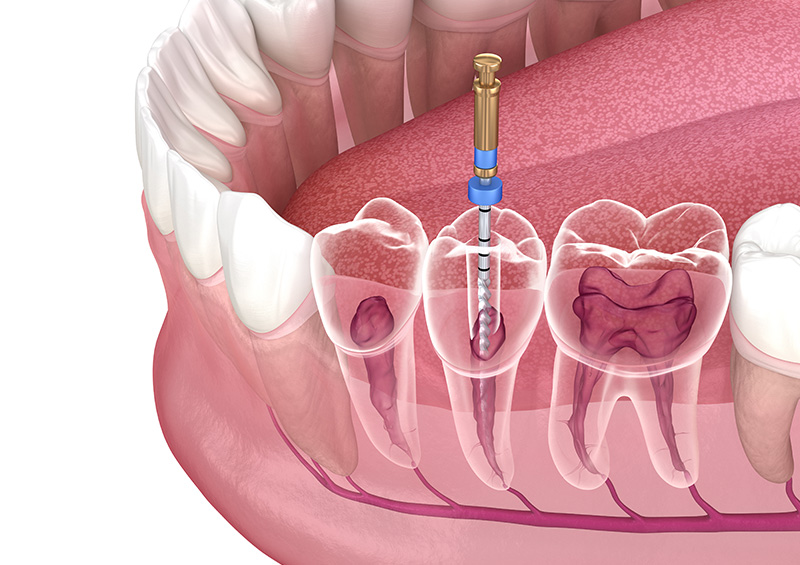

Our Treatments

Oral Surgery

Preventive & Restorative Dentistry